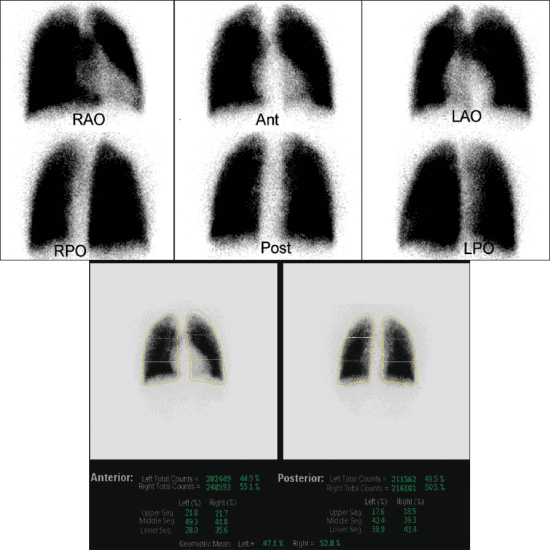

A lung perfusion scan is part of nuclear medicine scan. The scan is performed to look at the flow of blood. It shows how blood is flowing within your lungs. For this scan, you will be injected with radioactive albumin into your vein and the radioactive tracer is absorbed where blood flow is normal. The areas that are not getting blood do not absorb the tracer.